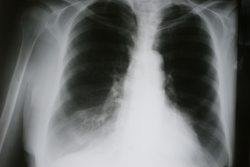

Ателектаз легкого: причины, симптомы и принципы лечения

Ателектаз легкого – патологическое состояние, при котором в легком образуется участок безвоздушной ткани со спавшимися альвеолами. Данный клинический синдром встречается у взрослых и детей. При этом он может быть врожденным и приобретенным.